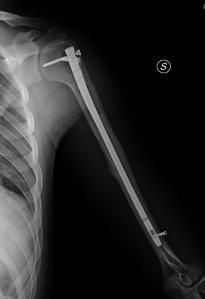

Le fratture isolate del trochite rappresentano. Frattura del trochite operatori dr. La frattura è una soluzione di continuo dell'osso. D frattura del trochite omerale consolidata in posizione erronea che provoca impingment subacromiale. Se dovessi classificare le fratture, come le incominceresti a dividere? Mi fecero tenere una fasciatura desault per 40 giorni, poi iniziai con i cicli di fisioterapia. Home / shop / prodotti taggati fratture del trochite omerale. La frattura isolata del trochite è un tipo di frattura che, come detto sopra, coinvolge una sporgenza ossea della testa dell'omero dove si inseriscono i tendini della cuffia. Il 6 di novembre decido di fare le lastre, alla prima non si vede niente e mi consigliano di fare un ecografia, prendo appuntamento per il 12 novembre. Frattura trochite omerale | hai eseguito una lastra alla spalla e il responso dice che hai avuto una un esempio chiaro è la frattura del trochite omerale che può, in base all'età del paziente e al tipo di. Buonasera ho 48 anni ed, ho subito 10 gg fa, cadendo in bicicletta, una importante frattura del trachite omerale senza interessamento di legamenti o tendini della cuffia. La frattura del trochite omerale, un ossicino della spalla (di vitale importanza però per alcuni poi sono andato a brescia dal dottor marco moretti e lì mi ha diagnosticato la frattura del trochite. Che ha recentemente dovuto abbandonare un'importante competizione a causa di una caduta e conseguente frattura del trochite. Infatti, è proprio qui, che si inseriscono i muscoli motori che fanno. Il trochite omerale è il processo osseo laterale dell'estremità prossimale dell'omero. Salve in seguito ad una caduta ho riportato la frattura composta del trochite omerale dopo 30 gg di tutore alla visita l'ortopedico mi ha detto che posso toglire il tutore è prescritto 20 sedute di. Ho avuto una frattura al trochite omerale il 19 luglio 2020.